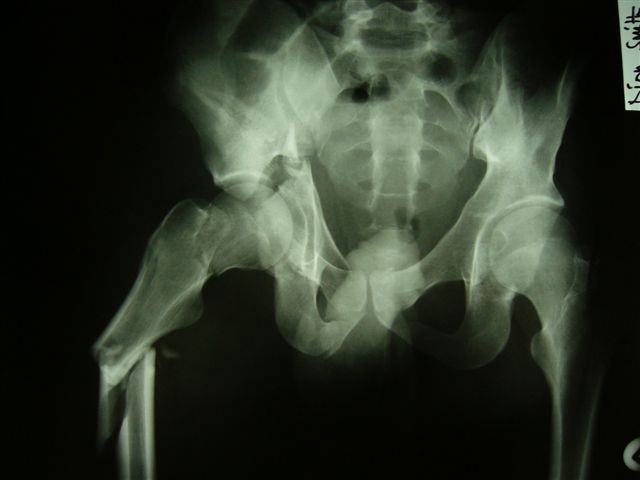

12.04.04

02.06.04